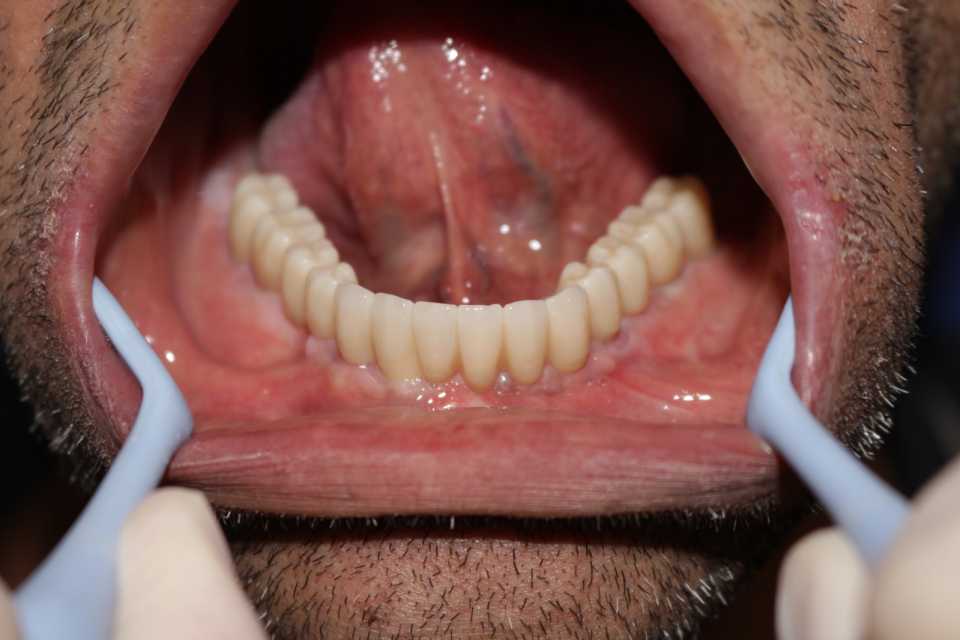

Pacientul Nicu D., în vârstă de 50 de ani, s-a prezentat în cabinet cu o edentație totală mandibulară în urma unei boli parodontale.

Împreună cu pacientul am hotărât realizarea unei lucrări protetice fixe inșurubabile pe 6 implanturi (implanturi Paltop). Lucrarea a fost realizată din ceramică pe zirconiu.

Implantul Paltop oferă posibilitatea realizării unor lucrări cu o estetică impecabilă și o afectare minimă a țesuturilor la locul implantării. Profilul concav al bontului protetic ajută la formarea unui țesut gingival dens la nivelul legăturii transgingivale scăzând vizibilitatea bontului.